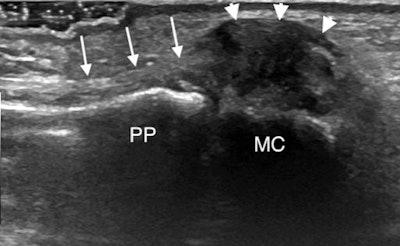

Lesions such as avulsion or an undisplaced intrasubstance tear of the ulnar collateral ligament usually heal spontaneously. However, in about a third of cases, the torn ligament retracts proximally and displaces superficial to the adductor pollicis aponeurosis. This injury is known as a displaced tear or Stener lesion, and the patient must undergo surgical repair to prevent permanent instability and premature osteoarthritis, McCarthy explained.

In an undisplaced tear in which the ligament looks thickened and hypoechoic often with a cleft extending through it, there is no significant proximal retraction, so the ligament appears symmetrically centered over the MCP joint. Dynamic imaging once again using joint extension and flexion will show the aponeurosis gliding over the thickened hypoechoic torn ligament. Meanwhile, in Stener lesions the torn ligament retracts proximal to the MCP joint to lie adjacent to the metacarpal head. The ligament has an asymmetrical appearance with a larger retracted proximal end, which looks like a round hypoechoic mass.

"The adductor aponeurosis will point into the retracted ligament and does not overlie it. This nodular appearance recalls the 'yo-yo on a string' sign visible at MRI with the aponeurosis making up the string extending into the retracted nodular ligament, which forms the ball of the yo-yo," McCarthy said. "You may also see the aponeurosis folding between the fibers of the torn ligament which are displaced superficial to the aponeurosis."

Again dynamic imaging will show the aponeurosis clashing into the retracted ligament that is displaced proximal and superficial to the aponeurosis, and this identification method should be preferred to radial stress. It is often useful to compare with the normal asymptomatic side to help clarify the picture and confirm the diagnosis, while keeping an eye out for an avulsion fracture, she concluded.